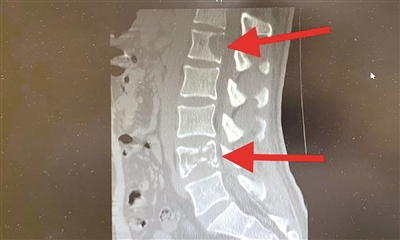

影像检查显示肺癌晚期伴骨转移

李先生来医院时,已经走不了路了,是用担架抬进来的。经过PET-CT等详细检查,诊断为肺癌晚期伴骨转移。

由于李先生目前的情况已经无法手术,我们组织多学科会诊(MDT),制订了个体化治疗方案。以经皮穿刺腰1、4椎体后凸成形术稳定受损椎体,同时配合止痛和营养神经治疗,显著缓解疼痛症状。随后进行腰椎姑息性放疗和靶向治疗。经过系统治疗,李先生的病情得到明显改善,现在已经能够自主行走了。